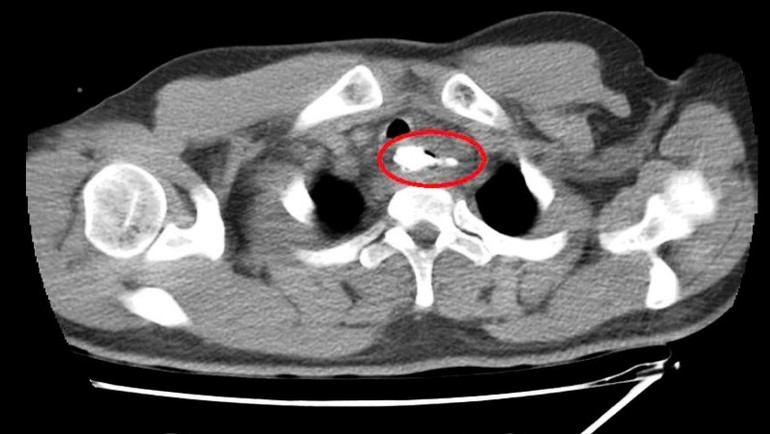

Qua thăm khám lâm sàng, chụp cắt lớp vi tính vùng cổ, nội soi mềm thực quản, các bác sĩ phát hiện một dị vật là mẩu xương lớn, nằm ở thực quản đoạn ngực có khả năng gây thủng thực quản, tổn thương nghiêm trọng đến các cơ quan xung quanh.

Ngay lập tức, bệnh nhân được chuyển đến phòng mổ để tiến hành nội soi thực quản ống cứng lấy dị vật dưới gây mê. Quá trình phẫu thuật kéo dài hơn một giờ, đội ngũ nhân viên y tế của các chuyên khoa: Ngoại Nhi Cấp cứu bụng, Tai Mũi Họng, Gây mê hồi sức tại Bệnh viện Trung ương Huế phối hợp thực hiện, khéo léo lấy bỏ dị vật mà không làm tổn hại thêm đến thực quản. Dị vật là mẩu xương heo, có mấu nhọn, kích thước 30x41mm, nằm ở thực quản đoạn ngực, cách cung răng trên 20cm.